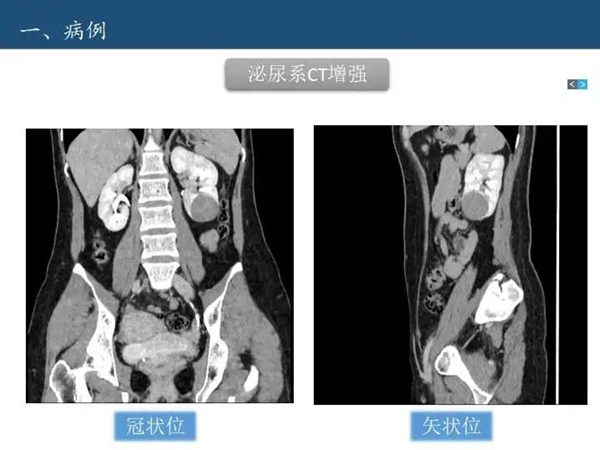

病例讨论—肾脏囊性病变Bosniak分级